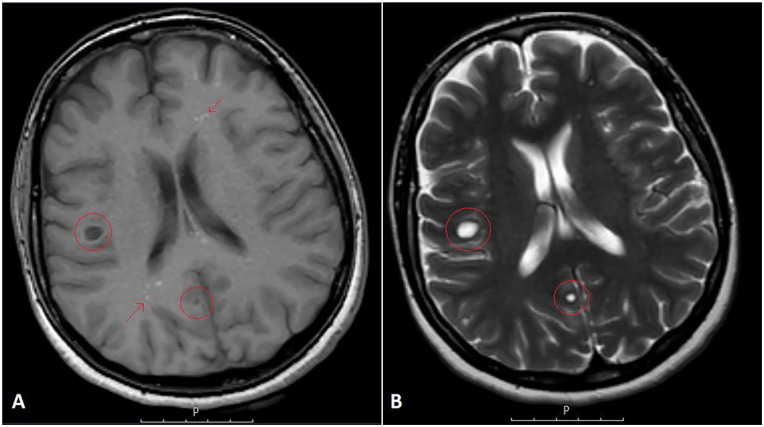

肺神经内分泌肿瘤包括神经内分泌癌和神经内分泌肿瘤(NETs)。net也被称为类癌(CaTs),分为典型类癌和非典型类癌(AC)。肺部cat常转移到不同部位,包括局部淋巴结、肺、肝和骨;然而,转移到大脑是相对罕见的。早期出现脑转移的患者更是罕见。我们报告一例50岁的女性患者,她最初表现为神经系统症状和磁共振成像结果提示多发性硬化症。尽管最初的治疗是多发性硬化症,但进一步的评估发现了一个罕见的支气管肺AC肿瘤转移到脑部的病例。本病例强调了在出现非典型神经症状的患者中考虑转移性疾病的重要性,特别是当初始治疗未能产生预期结果时。我们的文献回顾显示了7例最初表现为脑转移的cat,我们的患者是所有已发表病例中最年轻的。

Neuroendocrine neoplasms of the lung include neuroendocrine carcinomas and neuroendocrine tumors (NETs). NETs are also known as carcinoid tumors (CaTs), which are categorized as typical carcinoid and atypical carcinoid (AC). Pulmonary CaTs often metastasize to various sites, including regional lymph nodes, lungs, liver, and bone; however, metastasis to the brain is relatively rare. It is even rarer for patients with CaTs to present with signs of brain metastasis initially. We report the case of a 50-year-old female patient who initially presented with neurological symptoms and magnetic resonance imaging findings suggestive of multiple sclerosis. Despite initial treatment for multiple sclerosis, further evaluation uncovered a rare case of bronchopulmonary AC tumor metastasis to the brain. This case highlights the importance of considering metastatic disease in patients presenting with atypical neurological symptoms, especially when initial management fails to yield expected outcomes. Our literature review revealed 7 cases of CaTs initially presenting with brain metastases, with our patient being the youngest among all published cases.